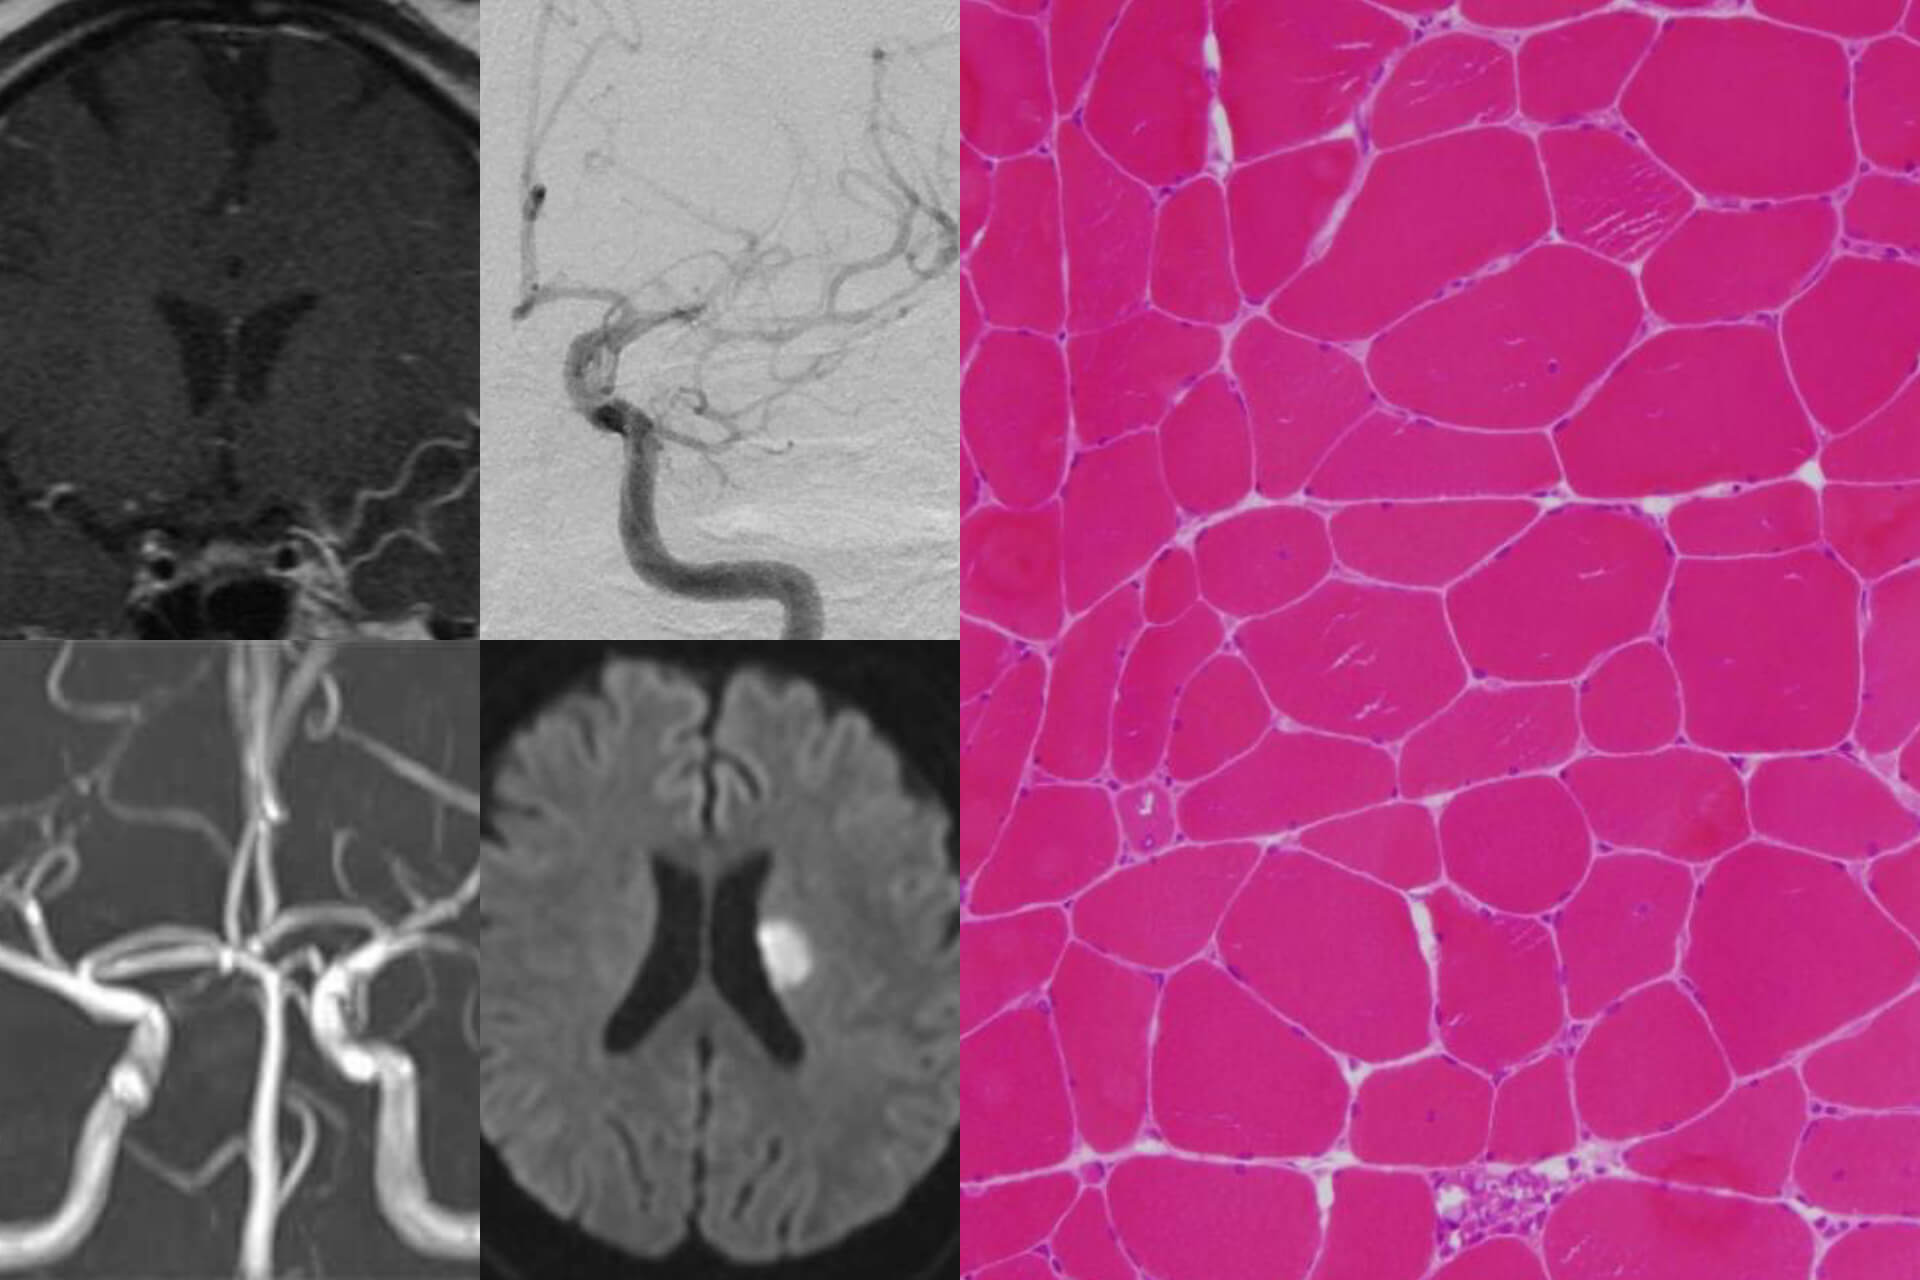

日常臨床では神経画像検査、生理学的検査などを用い診断を行い、最新の治療を目指し、患者に寄り添った診療を行うことを心がけています。診断に生検が必要な末梢神経障害や筋疾患では、本院の協力を得て施行しています。

脳卒中、パーキンソン病、パーキンソン症候群、認知症、てんかん、脳炎・髄膜炎、多発性硬化症、視神経脊髄炎、重症筋無力症、ギラン・バレー症候群、多発神経炎、ALS、脊髄小脳変性症、筋疾患など

CT、MRI、頸動脈エコー、核医学検査(SPECT、MIBG心筋シンチグラフィー、DATスキャン)、神経生理学的検査(脳波、末梢神経伝導検査、大脳誘発電位、筋電図)など